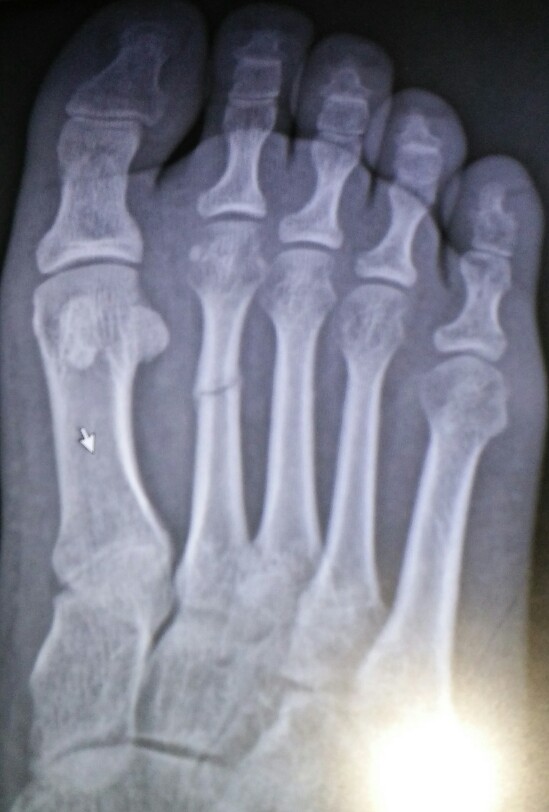

胫腓骨骨折 马上三个月可是痂还没有掉 痂上有个

一个月骨痂生长

长骨痂了吗?长得怎么样?可以拆石膏了吗?保守治疗石膏外固定的!

儿童骨折长出骨痂移位怎么办?